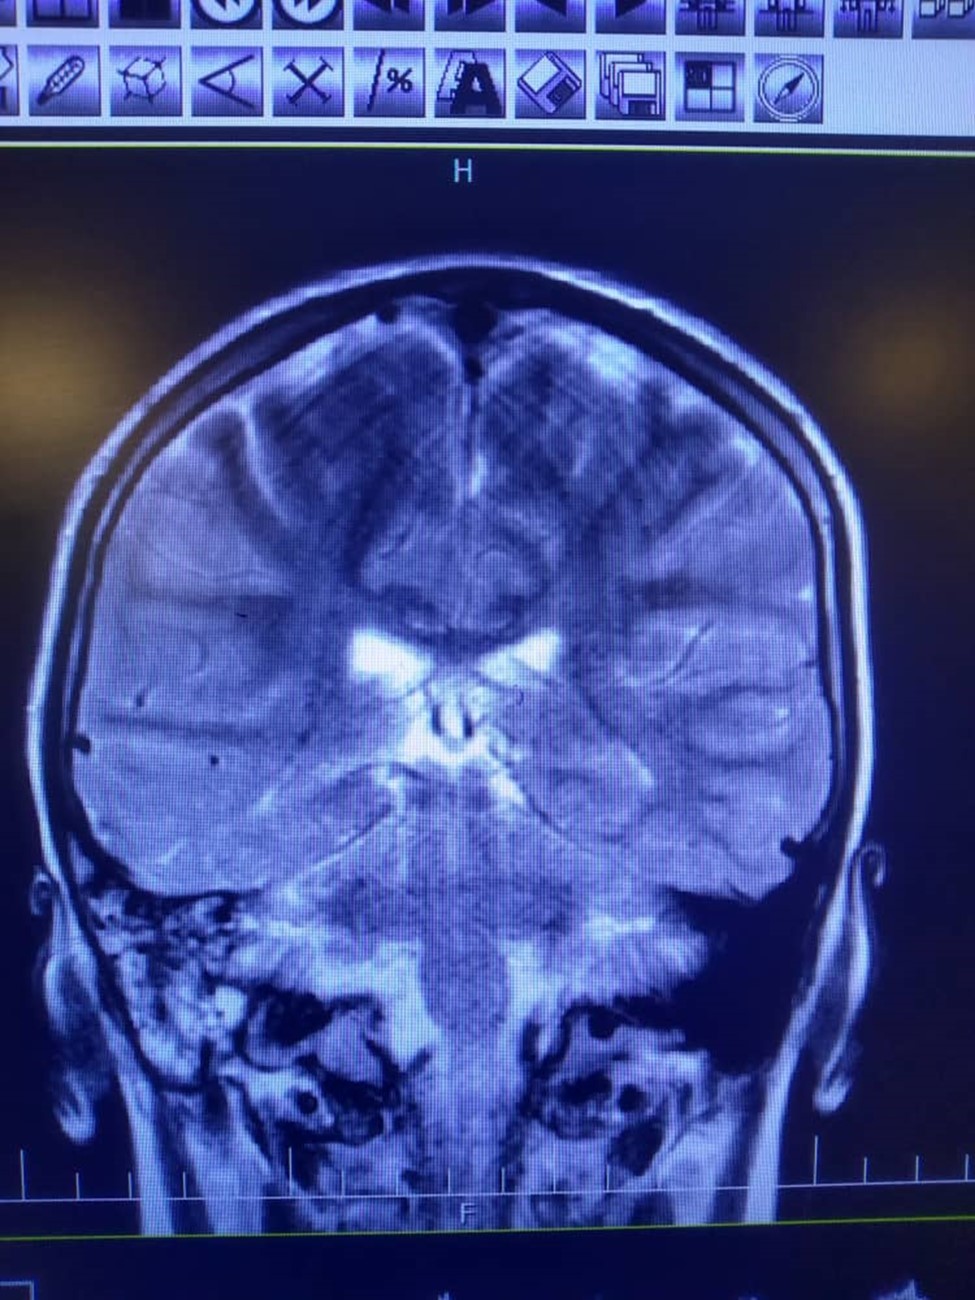

Despite the abnormal manifestation in mastoid cells, the audiometric examination was normal. Due to continuing the headache and right ear, the spiral HRCT of temporal bone without injection was requested. (Figure 2)

Figure 2.High signal intensity in both hemispheres is noted suggestive of meningitis. In T2 sequence there are hyper signal material left maxillary sinuse and bilateral frontal sinuses in favour of sinusitis, polyp and retention cyst in left maxillary sinus is noted. Effusion in right mastoidal air cell is noted.